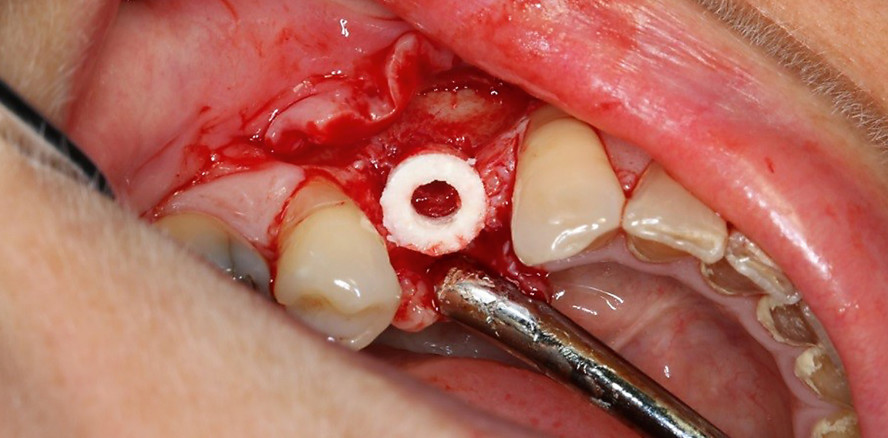

4. Implantation des allogenen Knochenrings, welcher zuvor in der Länge an die Defekttiefe angepasst wurde (Abb. 1b)

5. Fixierung des allogenen Knochenrings mit einem Implantat (Abb. 1c)

Das Implantat wurde etwa 1 mm unter dem Knochenniveau des allogenen Knochenrings eingebracht und im ortsständigen Knochen fixiert, wodurch auch der Knochenring immobilisiert wurde. Anschließend wurde eine Abdeckschraube in das Implantat eingebracht und das Augmentationsareal mit bovinem Knochenersatzmaterial überschichtet (cerabone®, botiss biomaterials) sowie mit einer resorbierbaren Barrieremembran aus nativem porcinen Perikard (Jason® membrane, botiss biomaterials) abgedeckt. Die hohe Volumenstabilität, welche das xenogene Knochenersatzmaterial bietet, gewährleistet ein fortbestehendes ästhetisches Erscheinungsbild des darüber befindlichen Weichgewebes. Die Augmentationsstelle wurde mit nicht resorbierbarem Nahtmaterial (SULENE® 4.0, Serag Wiessner) spannungsfrei und speicheldicht verschlossen, um einerseits einen durch mechanische Belastung induzierten Volumenverlust des augmentierten Knochens und zum anderen eine Infektion der Operationsstelle zu vermeiden. Nach dem Eingriff wurden der Patientin einige Instruktionen zur Nachsorge mitgeteilt und eine viertätige Antibiose verordnet. Eine radiografische Aufnahme, welche unmittelbar nach dem Eingriff durchgeführt wurde, zeigt die korrekte Positionierung des Implantats (Abb. 1d).